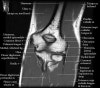

팔꿈치 관절의 MRI 단면 영상

- Sagittal section

1) Biceps Brachii tendon and Brachiallis muscles

2) Radial head for radiographically occult fractures

3) Distal Triceps tendon